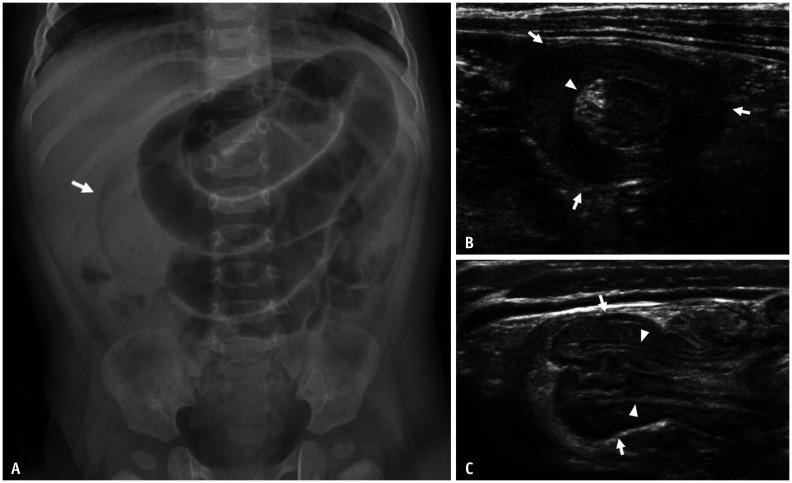

Gastrointestinal (GI) emergencies in neonates and infants encompass from the beginning to the end of the GI tract. Both congenital and acquired conditions can cause various GI emergencies in neonates and infants. Given the overlapping or nonspecific clinical findings of many different neonatal and infantile GI emergencies and the unique characteristics of this age group, appropriate imaging is key to accurate and timely diagnosis while avoiding unnecessary radiation hazard and medical costs. In this paper, we discuss the radiological findings of essential neonatal and infantile GI emergencies, including esophageal atresia and tracheoesophageal fistula, hypertrophic pyloric stenosis, duodenal atresia, malrotation, midgut volvulus for upper GI emergencies, and jejunoileal atresia, meconium ileus, meconium plug syndrome, meconium peritonitis, Hirschsprung disease, anorectal malformation, necrotizing enterocolitis, and intussusception for lower GI emergencies.

新生儿和婴儿的胃肠道(GI)急症涵盖了从胃肠道的开始到结束的各个方面。先天性和后天性疾病都可能导致新生儿和婴儿出现各种胃肠道急症。鉴于许多不同的新生儿和婴儿胃肠道急症的临床发现具有重叠或非特异性,以及该年龄段的独特特征,适当的影像学检查对于准确和及时的诊断至关重要,同时避免不必要的辐射危害和医疗费用。在本文中,我们讨论了基本的新生儿和婴儿胃肠道急症的放射学表现,包括食管闭锁和食管气管瘘、肥厚性幽门狭窄、十二指肠闭锁、肠旋转不良、胃上消化道急症,以及空肠回肠闭锁、胎粪性肠梗阻、胎粪栓综合征、胎粪性腹膜炎、先天性巨结肠、肛门直肠畸形、坏死性小肠结肠炎和肠套叠等下消化道急症。